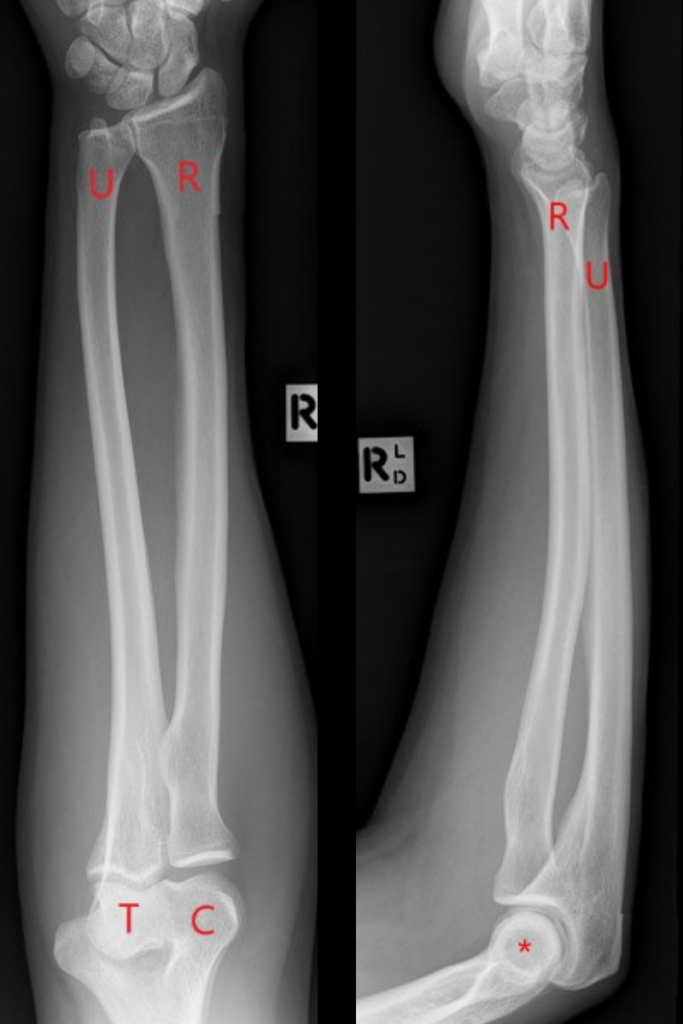

Figure 1 from Radius and Ulna Stress Fractures in a Patient with Radius Ulna Hairline Fracture A forearm fracture can occur in one or both of the forearm bones. Other fractures, such as proximal ulna fractures of the coronoid and. Some of the causes include falls on the forearm or outstretched arm and direct impact from an object to the forearm. Diagnosis is made clinically and radiographically with. When only one bone is broken, it is. Radius Ulna Hairline Fracture.